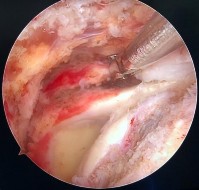

Hình phụ lục 2B:Hình ảnh rách rất rộng gân trên gai, dưới gai, khoảng gian chóp xoay; hình ảnh khâu khép rìa gân rách.

(Nguồn: BN nghiên cứu)